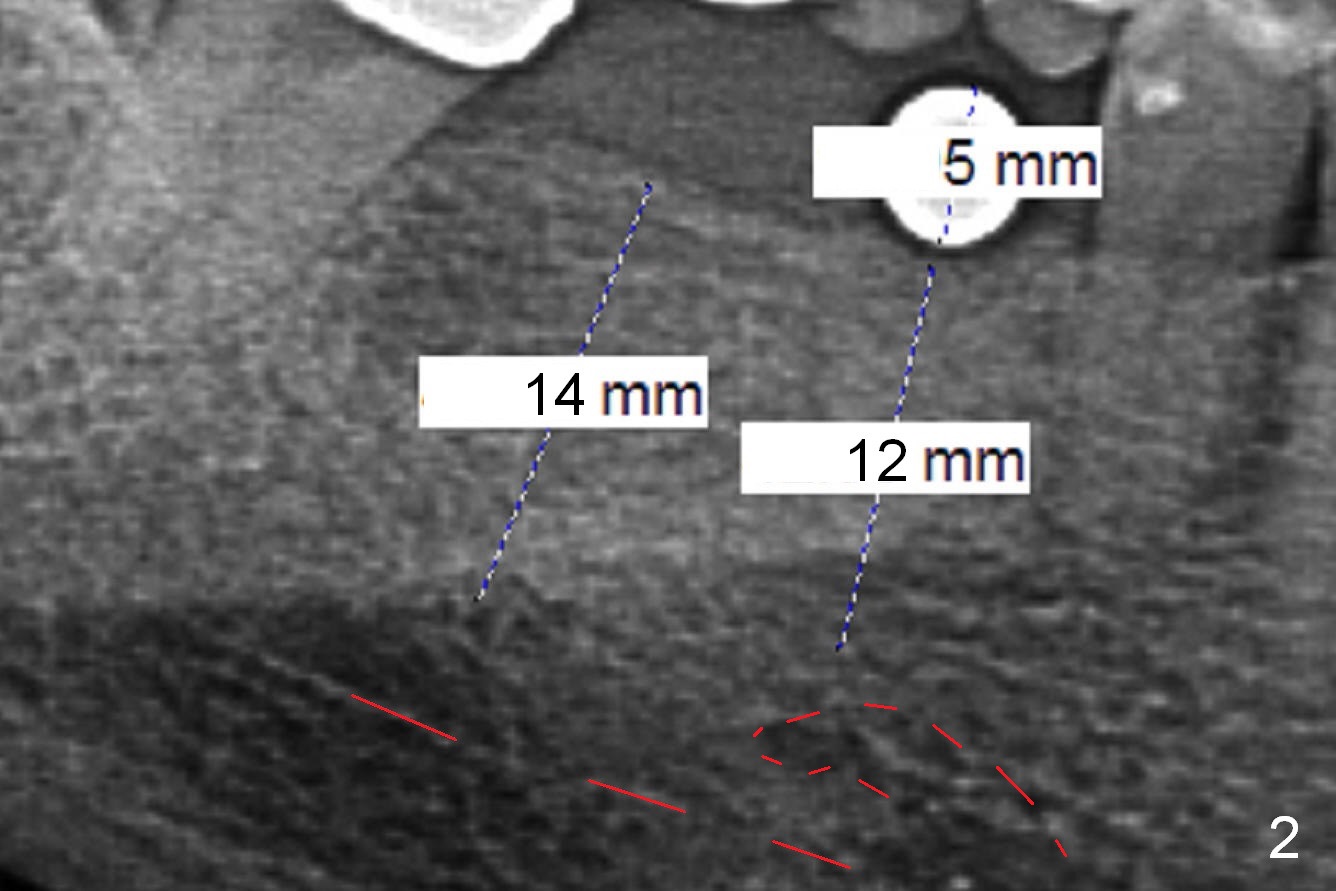

A 64-year-old woman requests implant placement at #29 and 30. There appears to be bone graft at the site of #29 (Fig.1). The ridge at these sites is moderately atrophic. The diameters of the implants will be determined by using Implant Positioners. Use Magic Split if needed. To avoid the Inferior Alveolar Nerve and Mental Nerve (Fig.2 red dashed line), initial depths at #29 and 30 are 10 and 12 mm.